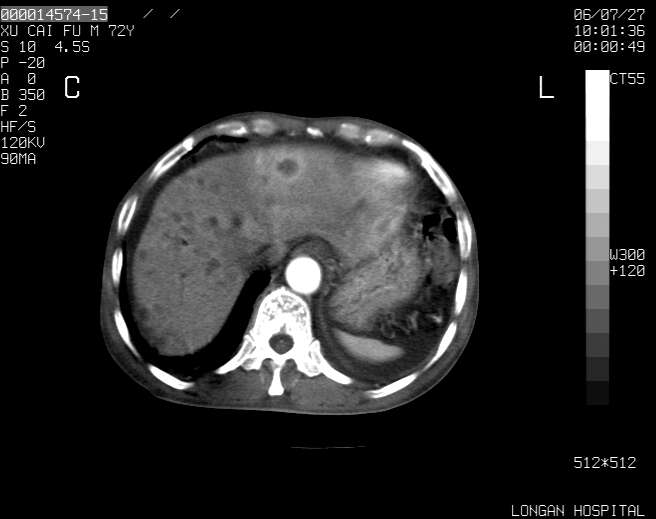

以下是引用winter在2006-7-30 20:14:00的发言:[br]1、考虑胆囊癌伴胆道侵犯并高位胆道梗阻、肝内多发转移、腹膜后淋巴结转移。[br]2、右肾轻度积水。[br]3、老人家72岁了胰腺头体尾部均较饱满,不过未见密度异常及其他异常征象。[br]4、腹水。

以下是引用jiajie在2006-7-31 7:10:00的发言:[br]考虑肝转移瘤,腹膜后淋巴结增大。[br]胃癌不能除外,建议胃镜检查。